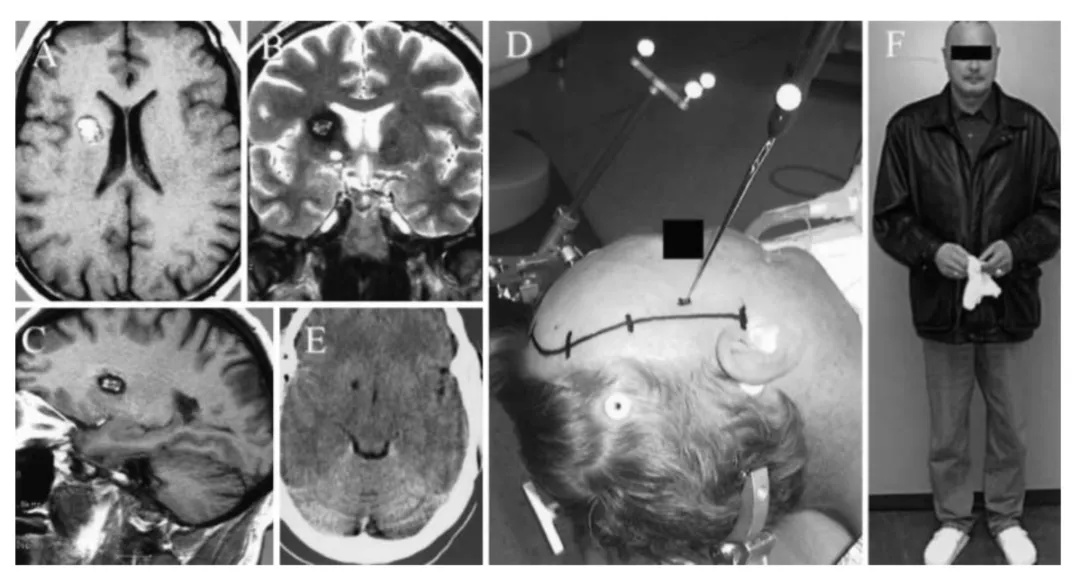

▼巴教授基底神经节海绵状血管瘤,54岁男性。该患者在神经导航的帮助下进行手术。A-C,术前MR图像显示右侧尾状核海绵状血管瘤。D,神经导航定位、皮肤切口等。E,海绵状血管瘤完全切除后的术后CT扫描。F,术后10天无神经功能缺损。